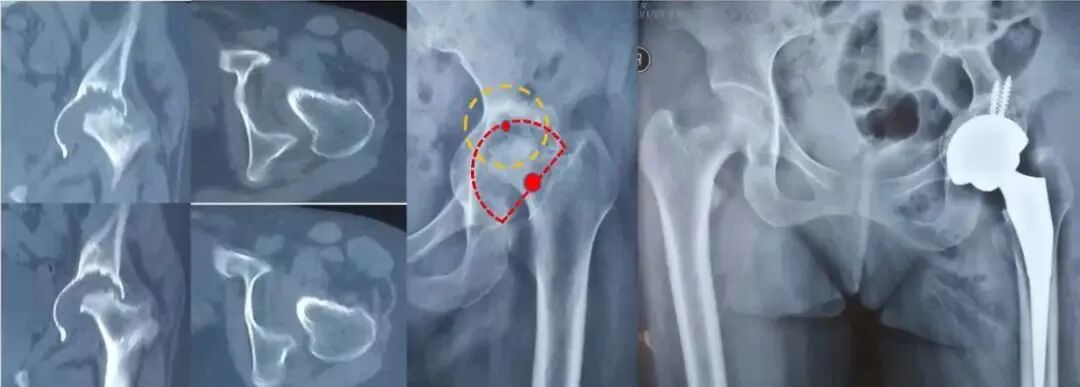

股骨近端形态与假体选择(Door分型)

股骨近端发育异常与手术方案选择:最常见畸形为DDH患者的髓腔细小与前倾角増大,需要用到特殊假体如组配柄,或者小尺寸远端固定柄,甚至需要做股骨近端成形,在设计髋臼前倾角时需适当减小,以保持联合前倾角在合理范围内(S-R○M, Wagner SL,Wagηer Cone)。

髋臼三柱组成:髋臼假体稳定性最重要靠前后壁“夹持”力量稳定。

术前评估——髋臼侧评估

髋中心内移程度和泪滴骨溶解程度:实际反映髋臼底部(中央部、内壁)的缺损深度及范围。

“Ⅰ度”旋转中心在Kohler线外侧

“轻度泪滴溶解”外侧缘少量股缺失

“Ⅱ度”Kohler线与骨盆内侧皮质处

“中度泪滴溶解”指外侧缘完全缺失

“Ⅲ度”旋转中心移至盆腔内

“重度泪滴溶解”外侧缘与内侧缘都有股缺失

术前评估——髋臼磨损或缺损程度

ParproskyⅠ型:极少量骨量丢失,髋臼壁磨损、变形,髋臼承重结构及前后柱完整,髋关节旋前中心无移位,也就是腔隙性缺损。

处理原则:不需要特殊假体或工具的准备,手术相对简单。

ParproskyⅡa型:指中等骨量丢失,旋转中心上移<3cm,髋臼顶部结构完整,髋臼环不完整但能支撑髋臼杯半球结构。

ParproskyⅡb型:指中等骨量丢失,旋转中心出现上移及内移,移位<3cm,髋臼上缘有缺损,髋臼缘不完整,但前后壁能支撑髋臼杯半球结构。

ParproskyⅡc型:指中等骨量丢失,旋转中心内移,移位<3cm,髋臼内侧壁骨缺损,前后柱完整,髋臼缘不完整,但前后壁能支撑髋臼杯半球结构。